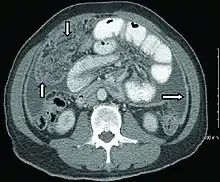

Chest X-ray and CT

In active pulmonary TB, infiltrates or consolidations and/or cavities are often seen in the upper lungs with or without mediastinal or hilar lymphadenopathy or pleural effusions ( tuberculous pleurisy). However, lesions may appear anywhere in the lungs. In disseminated TB a pattern of many tiny nodules throughout the lung fields is common - the so-called miliary TB. In HIV and other immunosuppressed persons, any abnormality may indicate TB or the chest X-ray may even appear entirely normal.

Abnormalities on chest radiographs may be suggestive of, but are not necessarily diagnostic of, TB. However, chest radiographs may be used to rule out the possibility of pulmonary TB in a person who has a positive reaction to the tuberculin skin test and no symptoms of the disease.

Cavitation or consolidation of the apexes of the upper lobes of the lung or the tree-in-bud sign[8] may be visible on an affected patient's chest X-ray.[1] The tree-in-bud sign may appear on the chest CTs of some patients affected by tuberculosis, but it is not specific to tuberculosis.[8]